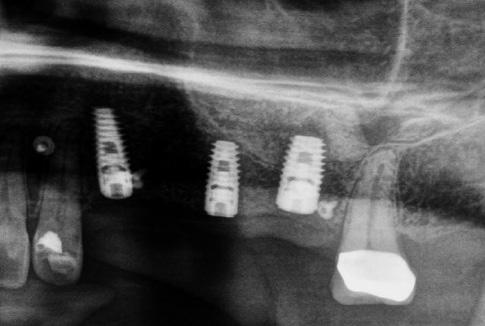

Case 1: Anterior tooth restoration with composite

Case 2: Posterior tooth restoration with composite

Restorations with BEAUTIFIL II LS, BEAUTIFIL Flow Plus X and OneGloss by Erik-Jan Muts, M.Sc., Netherlands